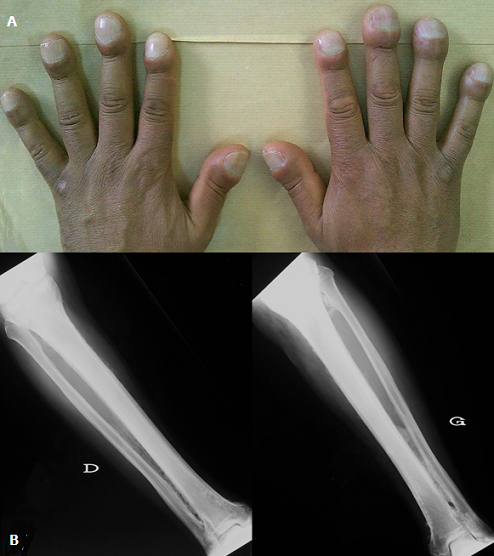

A 49-year-old man presented with arthralgias and effusion of the knees. His past medical syndrome revealed digital clubbing for 17 years (A) and an idiopathic Raynaud syndrome. Radiographs of the tibias and fibulas showed bilateral, symmetric, extended and multilayered periosteal thickening (B). Thoracic CT and cardiac ultrasound were normal, as well as inflammatory, hepatic and renal tests. Infectious investigations were negative. The diagnosis of primary idiopathic osteoarthropathy (HOA) was made with 3-year follow-up. HOA is a syndrome characterized by three clinical features: digital clubbing (also termed Hippocratic fingers), periostosis of tubular bones, and synovial effusions. HOA can be a primary entity, or can be secondary to extra skeletal conditions. Primary HOA is a rare disease, with male predilection. Hippocratic fingers show a distinctive bulbous deformity of the fingertips. It can be associated with large jointÂ’s effusions but there is neither synovial membrane hypertrophy nor inflammatory cell exudation. Radiographs may show an acro-osteolysis, periostosis of tubular bones. The tibia, fibula, radius, and ulna are the most commonly affected bones.